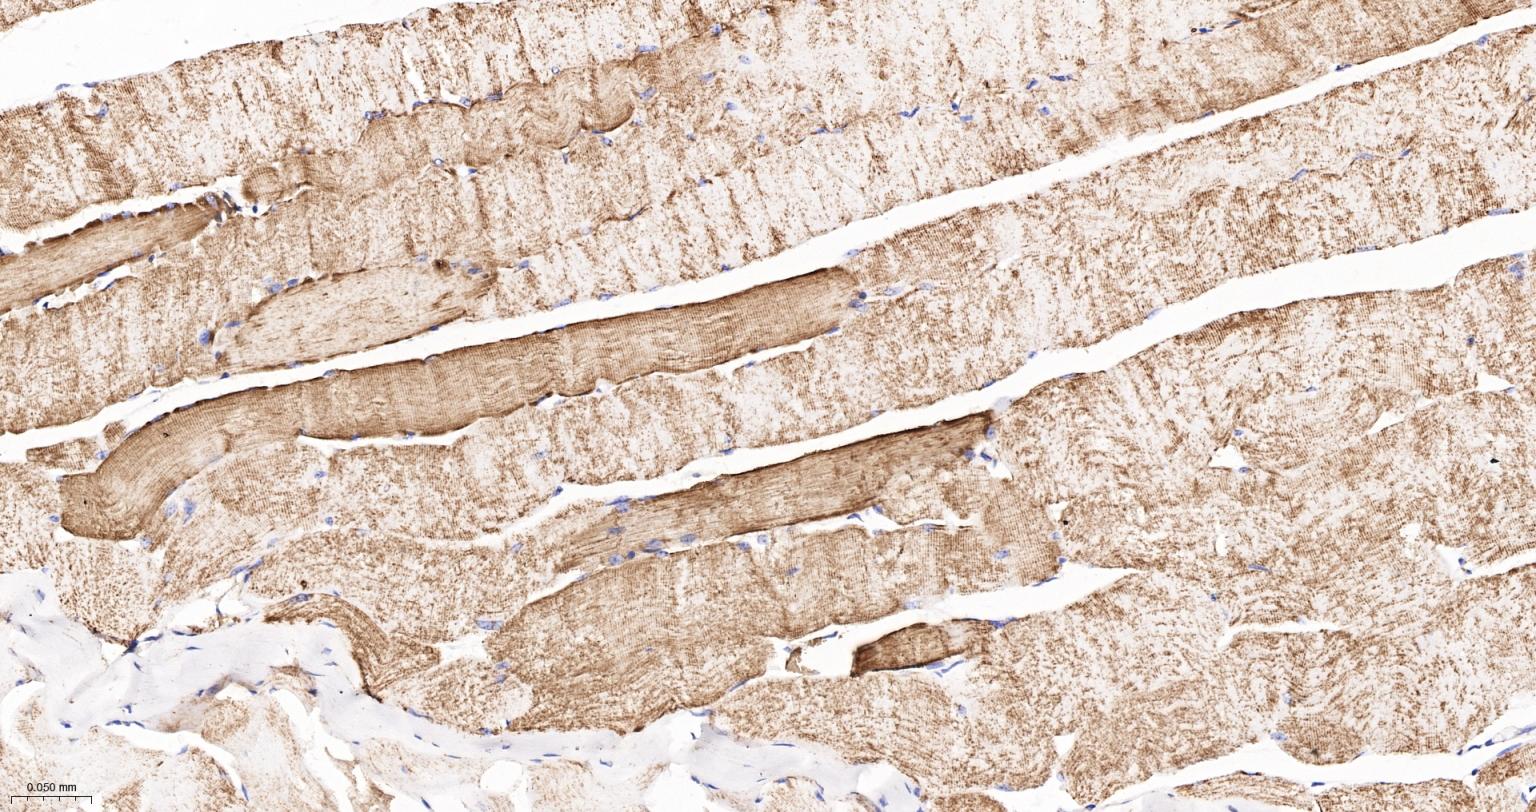

Paraformaldehyde-fixed, paraffin embedded Human Skeletal muscle; Antigen retrieval by boiling in sodium citrate buffer (pH6.0) for 15 min; The section was incubated with UQCRH Monoclonal Antibody, Unconjugated (bsm-62544R) at 1:200 overnight at 4°C, followed by conjugation to the bs-0295G-HRP and DAB (C-0010) staining.